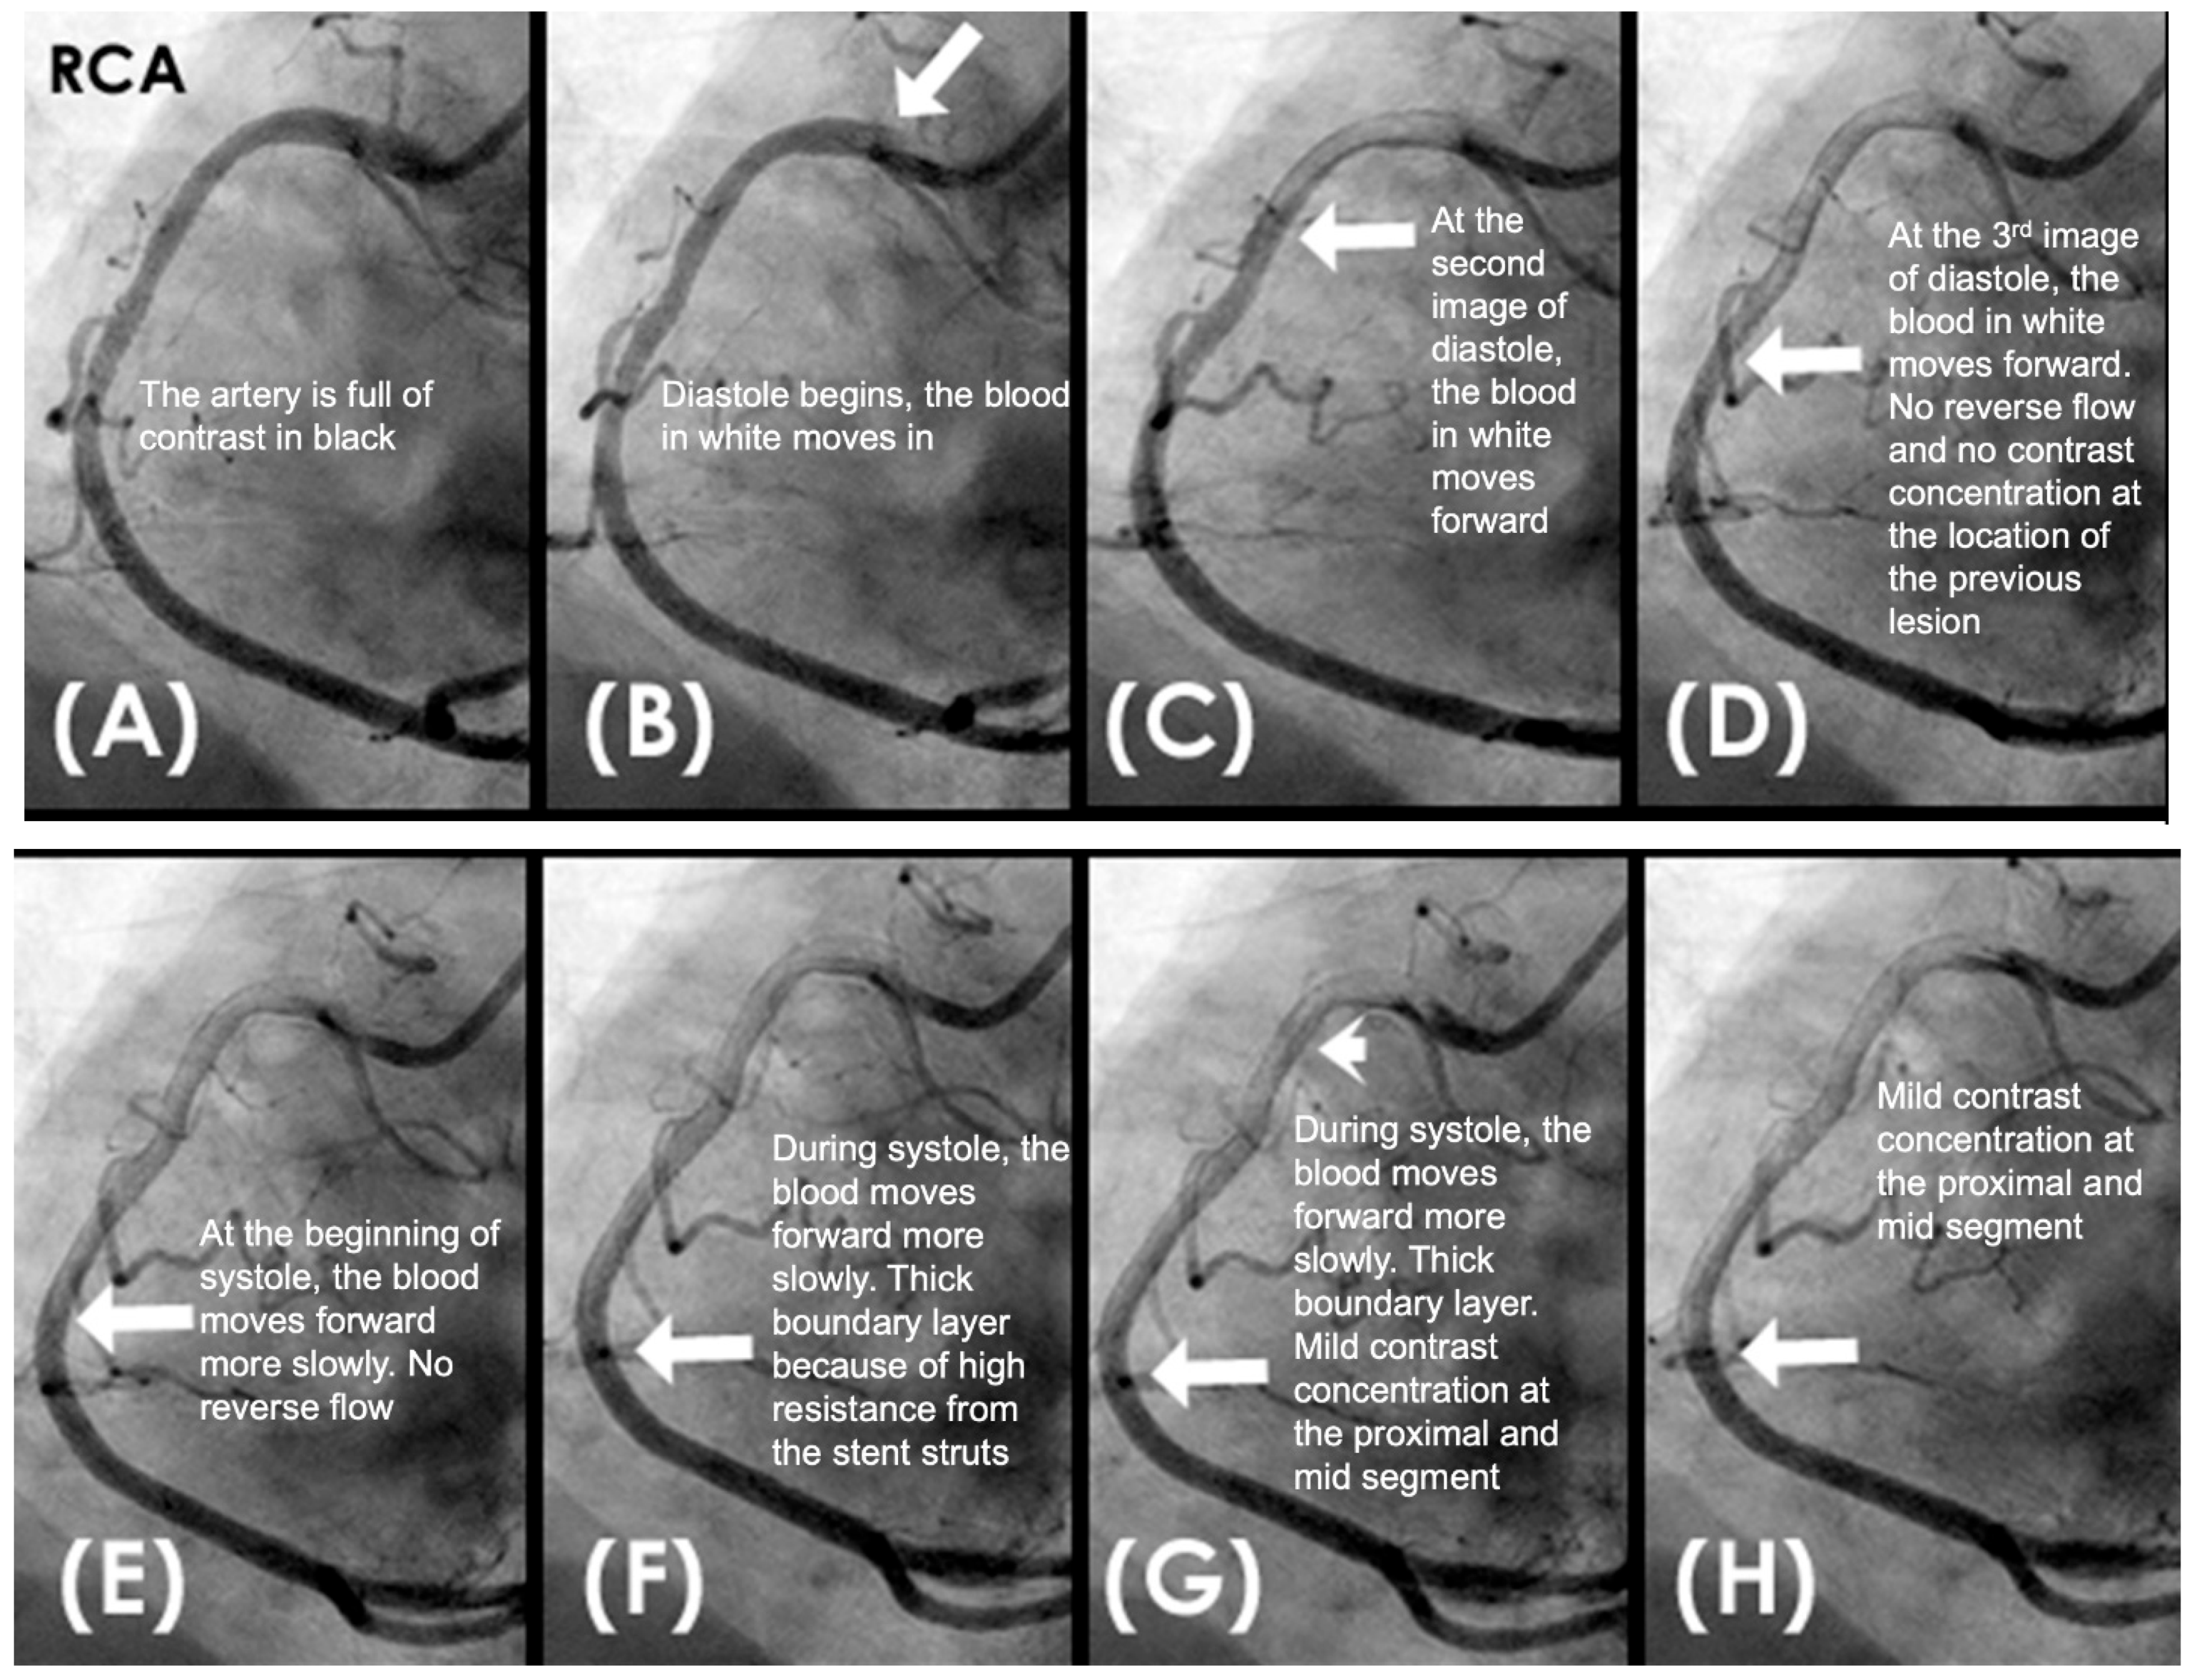

Dynamic Coronary Angiography. In a shift in strategy, our research adopted a novel approach by conceptualizing the cardiovascular system as an interconnected network of pipes and pumps, paving the way for the development of an innovative angiographic technique capable of capturing real-time coronary flow dynamics [2]. Drawing experiences from fluid mechanic engineering, where flow disturbances compromised the integrity of pipe surfaces, we hypothesized that analogous forces may damage the arterial intima. Accordingly, our analysis emphasized the characterization of blood flow—whether laminar, recirculating, disorganized—and its correlation with the initiation, progression, or regression of coronary lesion as seen in Figure 3 [3].

This approach defines baseline flow as antegrade and laminar, with deviations considered abnormal. Retrograde flow colliding with antegrade flow is a primary mechanism of vascular injury. A thick lateral contrast layer may indicate prolonged, subtle intimal damage, potentially leading to gradual lesion formation. Laminar flow supports long-term coronary patency.

Figure 3. (AD) Laminar flow. These four coronary images are of consecutive sequence. (A) This is the angiogram of the right coronary artery (RCA), which is filled with contrast in black. (B) The blood (in white) is seen well organized with sharp border and a pointed tip, typical for laminar flow, moving in (yellow arrow). (C,D) The blood is seen following the apex of the curves (yellow arrow). This is the laminar flow following the curves in a helical fashion.